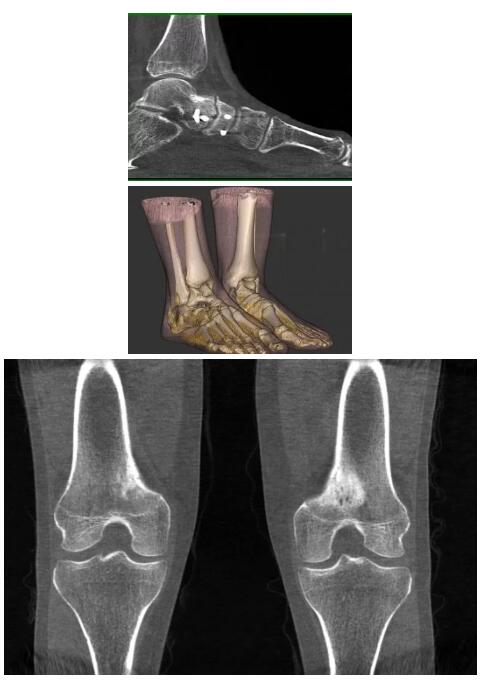

比如上面這款專用于足部和踝部掃查的CT成像系統(tǒng),患者在進(jìn)行CT掃查時只需要站在上面即可,雙腳站或者單腳站都可以,當(dāng)然,如果患者不是那么方便站著做完CT掃查,也可坐在上面。

這款CT掃查系統(tǒng)自帶屏蔽裝置,它的體積非常小,僅需要極小的空間即可,并不像常規(guī)CT那樣需要一間單獨(dú)的檢查室。此外,這種CT掃查的速度非???,僅需30秒左右可以完成檢查,輻射劑量相對常規(guī)的CT要少許多,尤其適合醫(yī)院的骨科使用。

而患者站著做足部或者踝部做CT檢查還有個好處是,可以檢查患者在負(fù)重的情況下,骨關(guān)節(jié)的真實(shí)情況,而躺著做CT掃查時未必能看出來。負(fù)重CT掃查特別是對于受傷的運(yùn)動員或者舞蹈員來說意義更大,能夠更準(zhǔn)確地評估傷情,幫助他們盡早復(fù)原。

以上介紹的CT均來自國外同一家公司,這些CT均配置了可視化軟件,可以進(jìn)行切片、3D重建以及大型CT附帶的所有典型的操作功能。

以下是這些“特立獨(dú)行”的CT所拍出來的圖像: